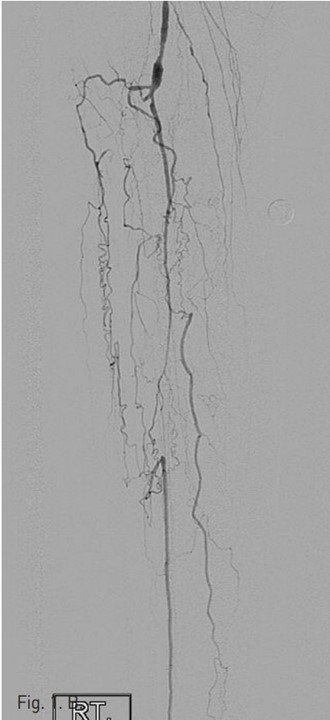

시술 당시 시행한 우측 하지 혈관조영술 (Fig. 1A)에서 right superficial femoral artery(SFA)의 mid-portion에 severe segmental stenosis가 있다. Popliteal artery는 segmental narrowing이 있고, tibio peroneal(TP) trunk 기시부에서부터 완전 폐색을 보이고 있으며, 우측 비골동맥과 후경골 동맥이 기시부에서부터 근위부 2/3 segment가 완전 폐색되어 있다(Fig. 1B).

Distal lower leg angiogram에서는 우측 비골동맥의 원위부가 collateral에 의해서 reconstitution되고 있고, 우측 후 경골동맥 역시 calcaneus tip level을 기준으로 상방 약 8 cm 길이에 걸쳐 내강이 확보되어 있고 혈류가 유지되어 있다. Plantar artery는 혈류가 유지되어 있다(Fig. 1C).

Fig. 1. B

B. The popliteal artery has multifocal luminal narrowing and tibioperoneal trunk is occluded.

Fig. 1. C

C. An angiography at level of ankle shows reconstitution of posterior tibial artery by collateral vessels and also shows patency of plantar artery.